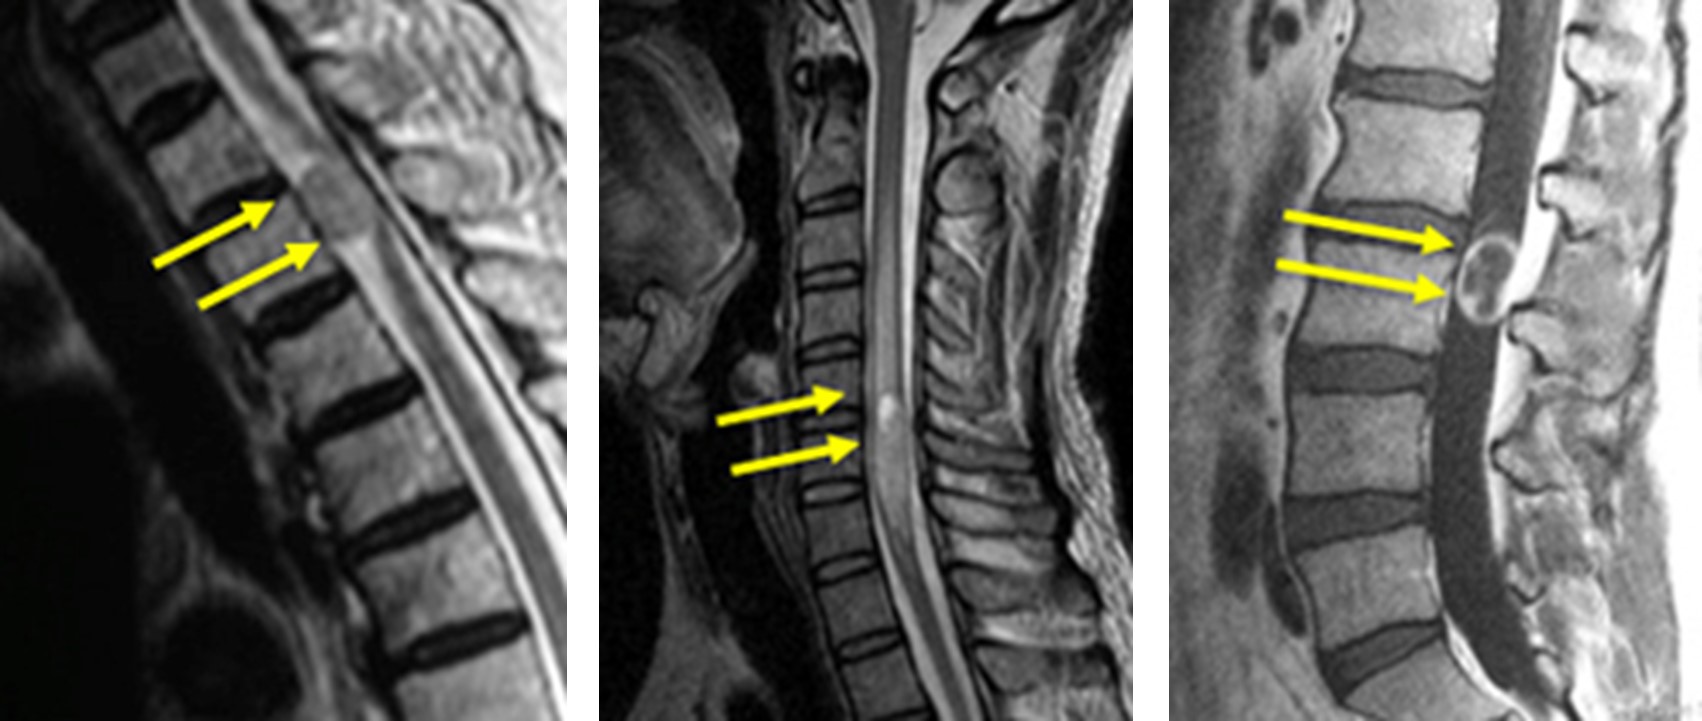

図 腫瘍はできる部位により、3つの種類に分類できます。

(左)脊髄髄外腫瘍

(まん中)脊髄髄内腫瘍

(右)馬尾腫瘍